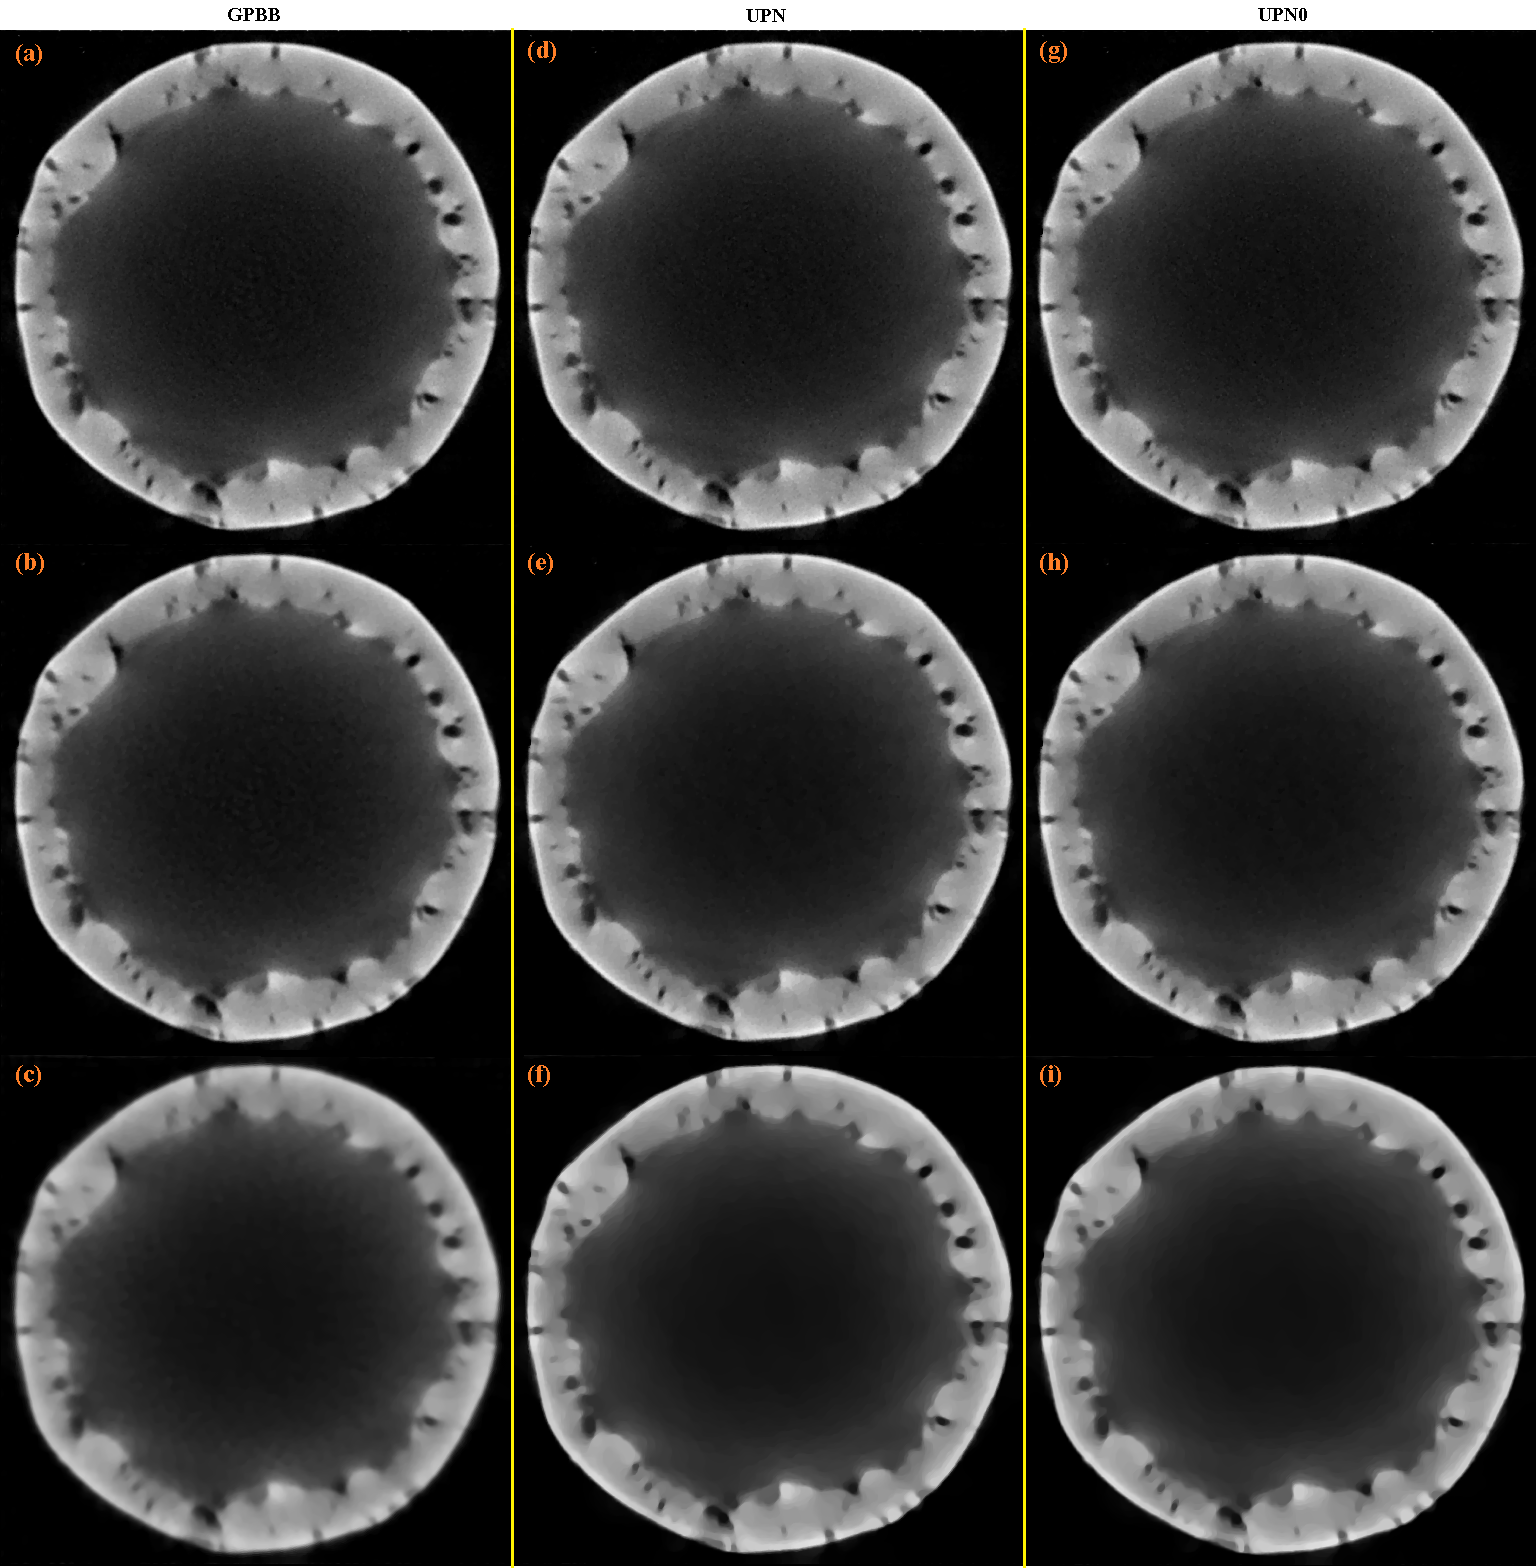

The reconstruction with the SbIR algorithm is shown in Fig. 2 (c), where in Fig. 2 (b) is shown the reconstruction obtained after the initialization step is applied. The reconstructions with the GPBB, UPN, UPN0 algorithms are shown in Fig. 3 when the regularization parameter α𝛼\alpha is 0.5, 5.0, or 50.0. In this example, the best reconstructions obtained with the GPBB, UPN, UPN0 algorithms are obtained when α=5.0𝛼5.0\alpha=5.0 (this means the middle row (b), (e) and (h) in Fig. 3).

Figure 3: (a), (b) and (c) are the results after 512 iterations for the GPBB method for α=0.5𝛼0.5\alpha=0.5, α=5.0𝛼5.0\alpha=5.0 and α=50.0𝛼50.0\alpha=50.0 respectively; (d), (e) and (f) are the results after 512 iterations for the UPN method for α=0.5𝛼0.5\alpha=0.5, α=5.0𝛼5.0\alpha=5.0 and α=50.0𝛼50.0\alpha=50.0 respectively; (g), (h) and (i) are the results after 512 iterations for the UPN0 method for α=0.5𝛼0.5\alpha=0.5, α=5.0𝛼5.0\alpha=5.0 and α=50.0𝛼50.0\alpha=50.0 respectively